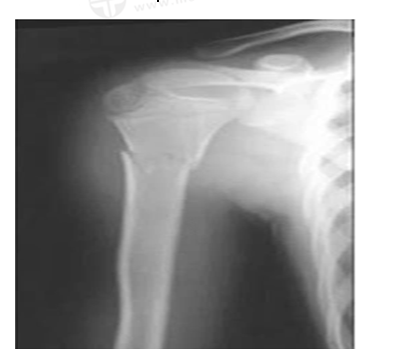

男,45歲,摔傷40分鐘,診斷為

A.右尺骨骨折

B.右橈骨骨折

C.右肱骨骨折

D.左肱骨骨折

E.右肱骨骨質(zhì)疏松

【答案】C